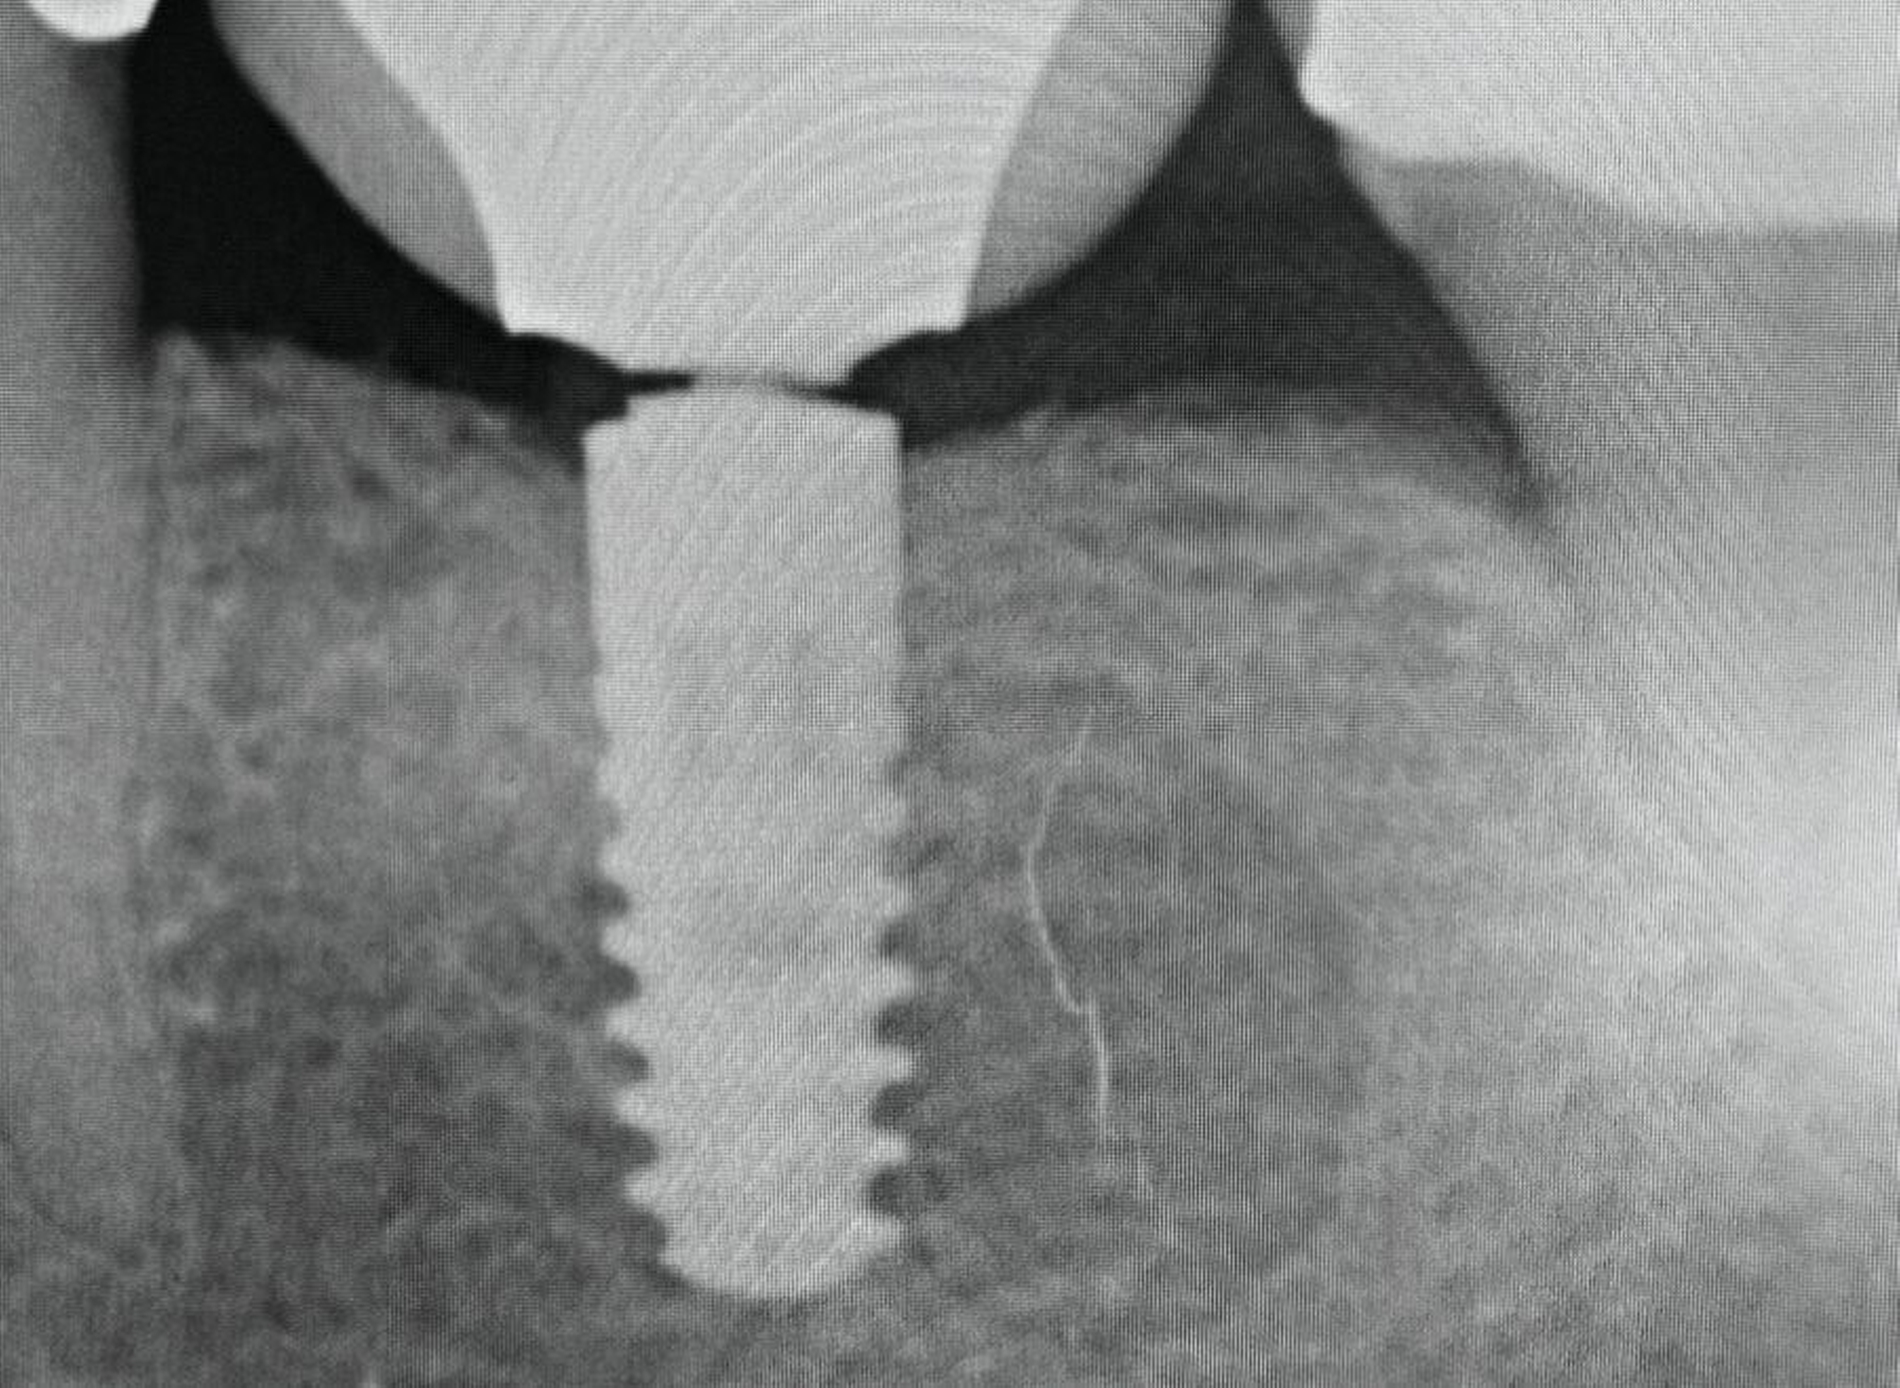

Das herstellerseitig empfohlene Vorgehen sieht vor, das Abutmentfragment zentral mit einem runden Bohrer oder Diamanten (Ø 1,2–1,4 mm) anzukörnen. Anschließend erfolgt die Bohrung mit einem speziellen Kernlochbohrer (Ø 1,8 mm, Tiefe circa 3 mm) bei 1800 U/min und unter Kühlung. Ein passender Extraktionsstift wird eingeschraubt und das Schraubenfragment mithilfe eines Ausdrehers entfernt. Für verbliebene Gewindehülsen stehen spezielle Ausdrehinstrumente zur Verfügung; in schwierigeren Fällen kann zusätzlich ein Spiralbohrer (1,4 mm) zum Einsatz kommen. Der finale Schritt besteht in der Nachbearbeitung des Innengewindes mit einem Gewindeschneider (M1,8). Zur Minimierung des Friktionswiderstands kann die Verwendung eines Gleitmittels (zum Beispiel Vaseline) hilfreich sein. Ein verkantungsfreies Arbeiten ist essenziell, um Instrumentenbruch und Implantatverlust zu vermeiden. Die radiologische Darstellung des Bruchs sowie die Situation nach Entfernung der Komponenten sind in den Abbildungen 3 und 4 dokumentiert.